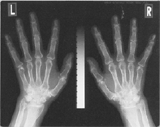

| 骨塩定量検査 |

骨塩量を調べる検査です。

手の指を骨塩測定のためのスケールと一緒にX線撮影をし、骨塩量を測定します。骨粗鬆症になってからではなく、若い間に検査を受け骨塩量を知っておくのが良いでしょう。 |